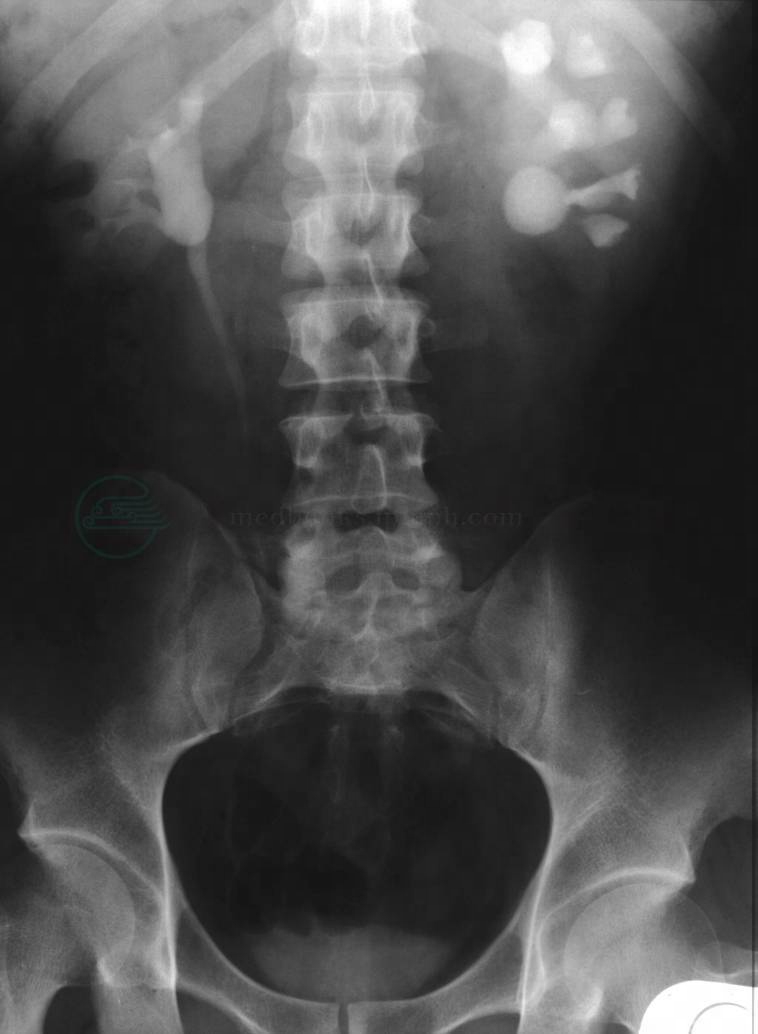

(二)泌尿系统平片

KUB是《CUA尿路结石诊疗指南》推荐的常规检查方法。摄片前需要排空肠道,摄片范围包括全泌尿系统,从11胸椎至耻骨联合。90%左右的肾结石不透X线,在KUB平片上可显示出致密影。KUB平片可初步判断肾结石是否存在,以及肾结石的位置、数目、形态和大小,并且初步地提示结石的化学性质(图2)。在KUB平片上,不同成分的结石显影程度从高到低依次为:草酸钙、磷酸钙和磷酸镁铵、胱氨酸、含钙尿酸盐结石。纯尿酸结石和黄嘌呤结石能够透过X线,在KUB平片上不显影,称为透X线结石或阴性结石。胱氨酸结石的密度低,在KUB平片上的显影比较浅淡。应当注意,KUB片上致密影的病因有多种,初诊时不能只根据KUB平片确诊肾结石,更不能只凭KUB就进行体外碎石、手术等治疗。需要结合B超、静脉尿路造影或CT等与肾结核钙化、肿瘤钙化、腹腔淋巴结钙化、胆囊结石等其他致密影相鉴别。KUB可用于肾结石治疗后的复查。

图2 左肾结石